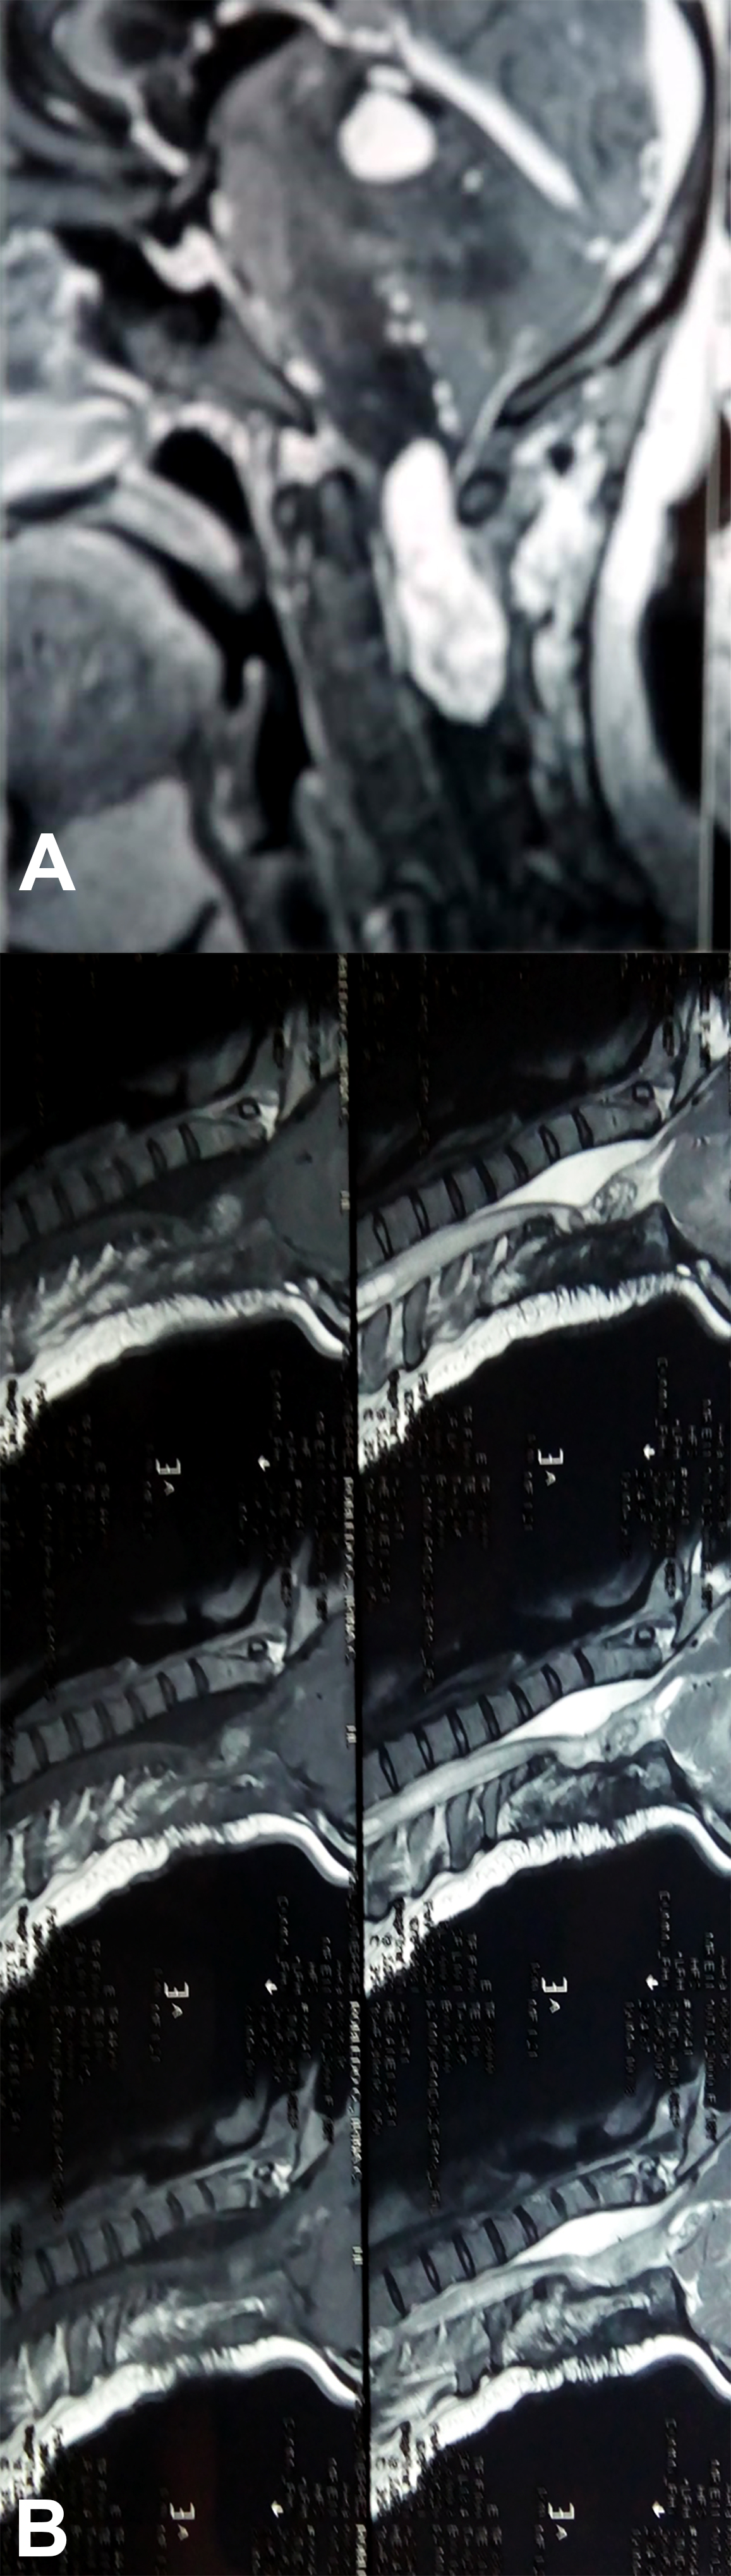

Es evidente que el límite entre el tejido medular y tumoral en las lesiones como los astrocitomas es indiscernible lo que dificulta la posibilidad de resección completa; en los tumores como los ependimomas esta diferencia es más franca y permite seguir un plano de disección seguro (Figuras 3, 4 y 5). Lo anterior condiciona nuestros resultados como han puntualizado diversos autores.5,8 El estado general previo a la cirugía requiere de una valoración juiciosa de las posibilidades de resección. Por ejemplo, el caso 12 (Figura 6) es una paciente portadora de Enfermedad de Von Hippel Lindau, Hemangioblastoma cervical biopsiado en otra institución del exterior del país, fijación de columna cervical y sindrome de Cushing por exceso de medicación corticoidea cuya cirugía debió suspenderse en dos oportunidades por la disminución de su capacidad ventilatoria. Con estos antecedentes y la delgada capa de tejido medular evidenciada intraoperatoriamente se optó por una resección subtotal. A los cuatro meses de la cirugía la paciente recuperó la marcha autónoma y demás parámetros clínicos.

Figura 4: Caso 10. Ependimoma cervical. La línea de puntos delimita la pared de la médula del tumor. Nótese la tinción de hemosiderina en la cara ventral medular.![]()

El caso del Neurocitoma cérvico dorsal (Figura 4), debido a su excepcionalidad, requiere un análisis particular lo cual realizaremos en una comunicación separada.

Figura 7: Caso 6. Astrocitoma Pilocítico cervical. Resección subtotal por caída de PESS. Falso Positivo.

Figura 8: Caso 12. Enf de Von Hippel Lindau. Hemangioblastoma cervical. Se observa otra lesión a nivel del Culmen cerebeloso.